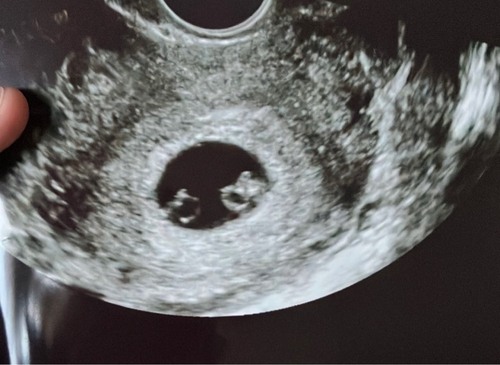

Geen domme vraag! Ik heb me ook in moeten lezen馃槉, Dan delen ze 1 placenta en 1 vruchtzak , komt voor bij 1 procent van de eeneiige tweelingen, meest risico volle zwangerschappen ivm dat de 2 navelstrengen in de knoop kunnen k

Raken..馃槉

Normaal zit er bij eeneiige tweelingen, nog een schotje tussen de baby鈥檚 en hier dus niet 馃槉

UPDATE; uiteindelijk geen momomono maar een monodia馃槉, 2aparte zakken maar delen wel de placenta